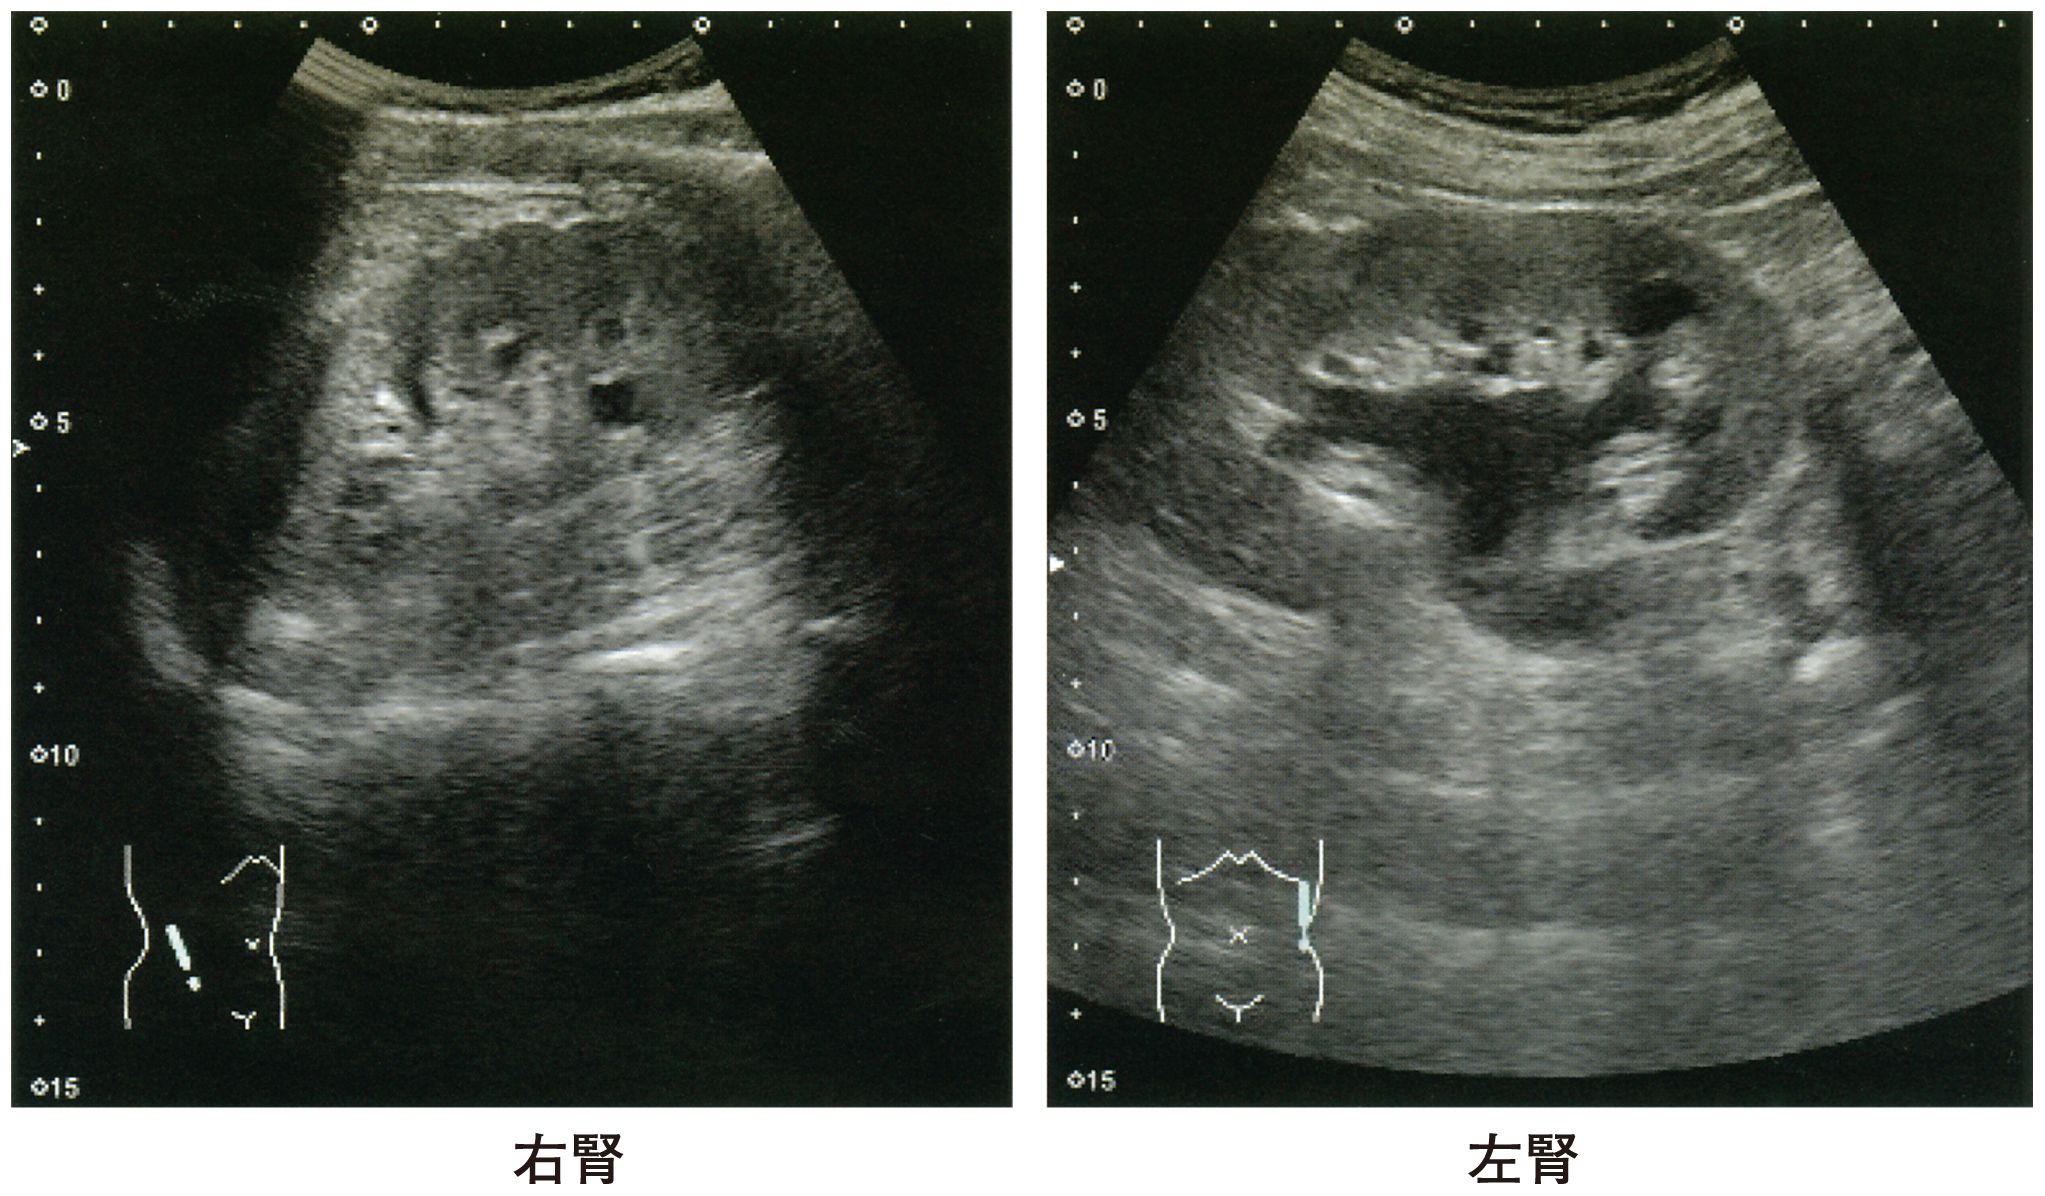

検査所見:尿所見:蛋白(-),糖1+,潜血(-),沈渣に異常を認めない。血液所見:赤血球489万,Hb 15.0g/dL,Ht 44%,白血球5,200,血小板17万。血液生化学所見:総蛋白7.7g/dL,アルブミン4.8g/dL,総ビリルビン0.8mg/dL,AST 26U/L,ALT 15U/L,LD 200U/L(基準124~222),ALP 67U/L(基準38~113),γ-GT 40U/L(基準13~64),アミラーゼ108U/L(基準44~132),CK 180U/L(基準59~248),尿素窒素14mg/dL,クレアチニン0.9mg/dL,尿酸6.6mg/dL,血糖130mg/dL,HbA1c 6.5%(基準4.9~6.0),Na 138mEq/L,K 4.1mEq/L,Cl 100mEq/L。CRP 0.1mg/dL。腹部超音波像を下に示す。